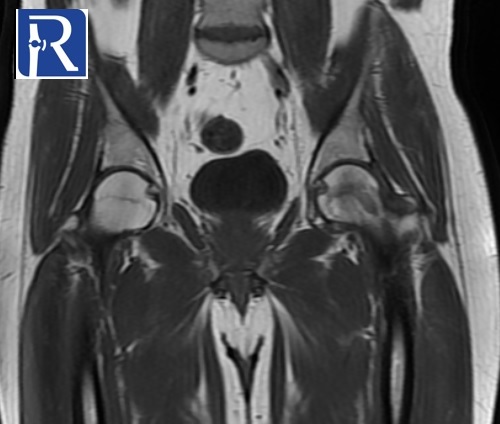

Image Details: AP X-Ray shows the diffuse decrease in density of left proximal femur, suggesting the osteopenia of left proximal femur. MR images shows the edema like signal changes in neck and head of left femur. Mild amount of effusion is present in left joint. Radiological (bone marrow edema and osteopenia of proximal femur) and clinical (young adult male with unilateral hip pain) suggest the diagnosis of transient osteoporosis of hip.